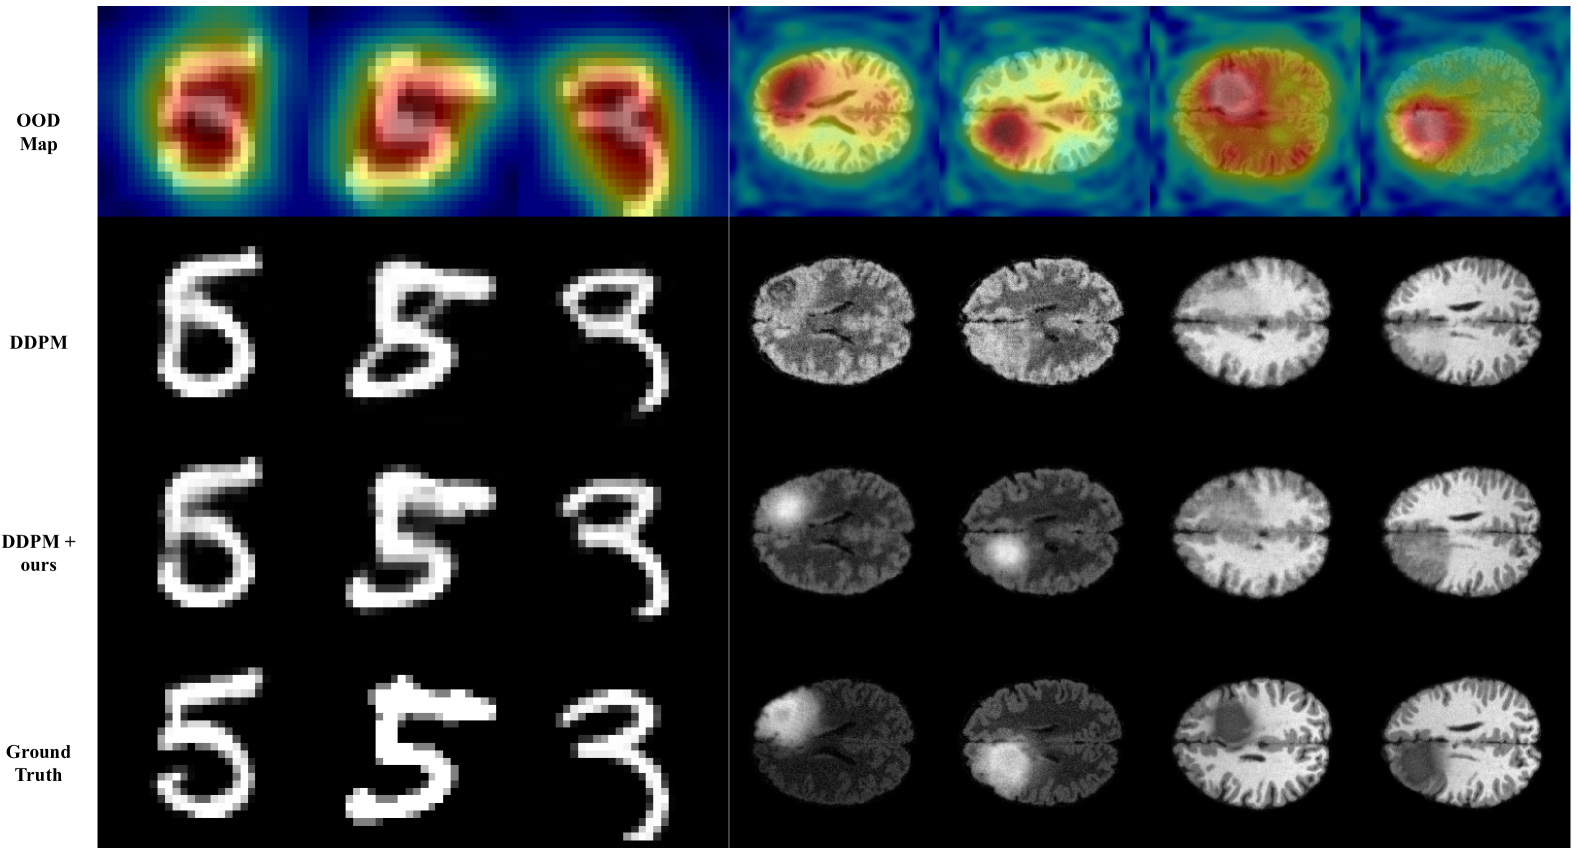

Fig 9 and 10 present visual comparisons across the MNIST, BraTS, and MVTec AD datasets. We conducted image super-resolution on MNIST and MVTec AD, and image translation on BraTS. The first rows in each figure display the predicted OOD maps of conditional images using our OOD detector, the second rows showcase hallucinated predictions from the DDPM model, and the third rows depict predictions produced by our Local Diffusion approach.

Refer to caption

Figure 9: Qualitative comparison on MNIST and BraTS(From top: Predicted OOD map, DDPM[10], DDPM with ours and ground truth).

The results demonstrate the efficacy of our Local Diffusion across different image modalities. As shown in the penultimate column’s example in Fig 9, our method maintains robust performance even in the presence of a noisy OOD probability map, alleviating the need for precise OOD region estimation and avoiding false positives.